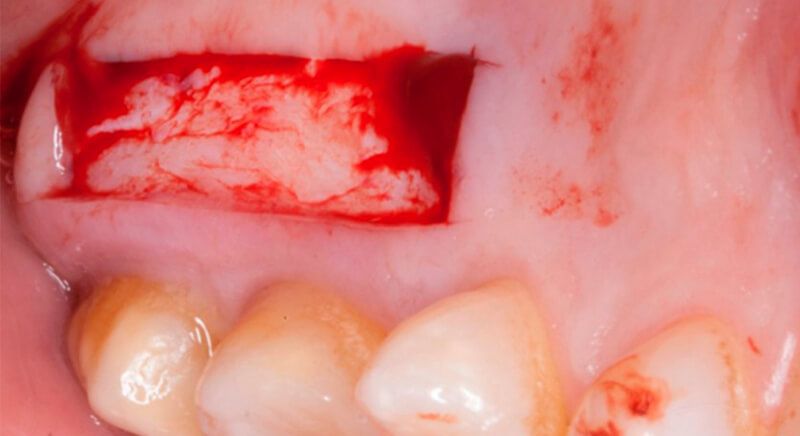

The socket was filled with a xenograft after the extraction and a graft of connective tissue was placed in the vestibular area of the two upper central incisors.

The tissue with epithelium was taken from the palate and de-epithelialized outside of the mouth. This obtains a lamina propria graft with better density and quality than if it were obtained with a single incision to the palate.